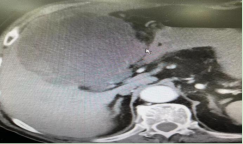

辅助检查:BNP正常。2022-10-15 腹部脏器(常规):肝内混合回声团:肝脓肿?请结合临床。2022-10-16 上腹部CT(平扫,增强扫描):肝右叶团块影,考虑感染性病变(大小约12.0*10.5*9.6cm)。

20221026日复查腹部CT提示:肝右叶团块影,考虑感染性病变,目前病变略较前增大(大小约12.0*11.5*10.2cm)。